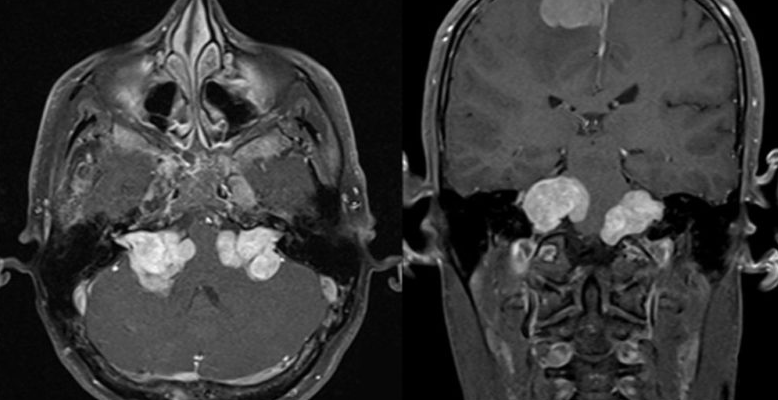

神经纤维瘤病2型,又称NF2,是一种染色体显性遗传疾病,临床表现多样,以双侧听神经瘤为其典型代表。据一项英国的研究报道,十年来英国西北部共发现NF2病人64例,年发病率为1/2355000。依照该比例测算,中国每年新发现的NF2病人大约为600例。基于人群的大样本统计,大约50%的NF2病人有家族史,说明NF2是一种遗传疾病。

听神经瘤通常生长缓慢,平均年增长率为2mm,但有时也会迅速生长,特别是年轻患者。当肿瘤在2cm以内时通常有耳科学症状,如耳鸣、听力下降、眩晕等,当肿瘤生长超过2cm时,肿瘤开始推压脑干、小脑及其它颅神经,患者逐渐出现耳神经学症状。肿瘤生长超过3cm后,脑干、小脑明显受压变形,患者出现明显的头痛、呕吐、走路不稳、面部麻木等神经学症状,脑疝可随时发生,导致病人死亡。

双侧听神经瘤NF2表现为颅内和脊髓多发性肿瘤,目前尚无根治办法。制定较佳治疗方案较困难,原因在于肿瘤分布广泛,个体差异大,在不增加面神经及有关神经并发症的前提下如何保留有用的听力是手术的难点和外科医生的追求。听神经瘤手术往往引起听力丧失、面瘫、暴露性角膜炎等严重的并发症。因此双侧听神经瘤NF2治疗方案的选择应依据肿瘤发生的部位、肿瘤大小、生长速度、每侧耳的听力水平、听力保留的可能性、肿瘤对脑干压迫的严重程度以及并发脑积水等情况综合考虑。由于NF2多种多样的表现形式,制定治疗方案应考虑到患者的的个体差异,有针对地采取灵活的个体化治疗方案。保守治疗只适用于病灶小、高龄以及手术治疗意愿不强的患者。